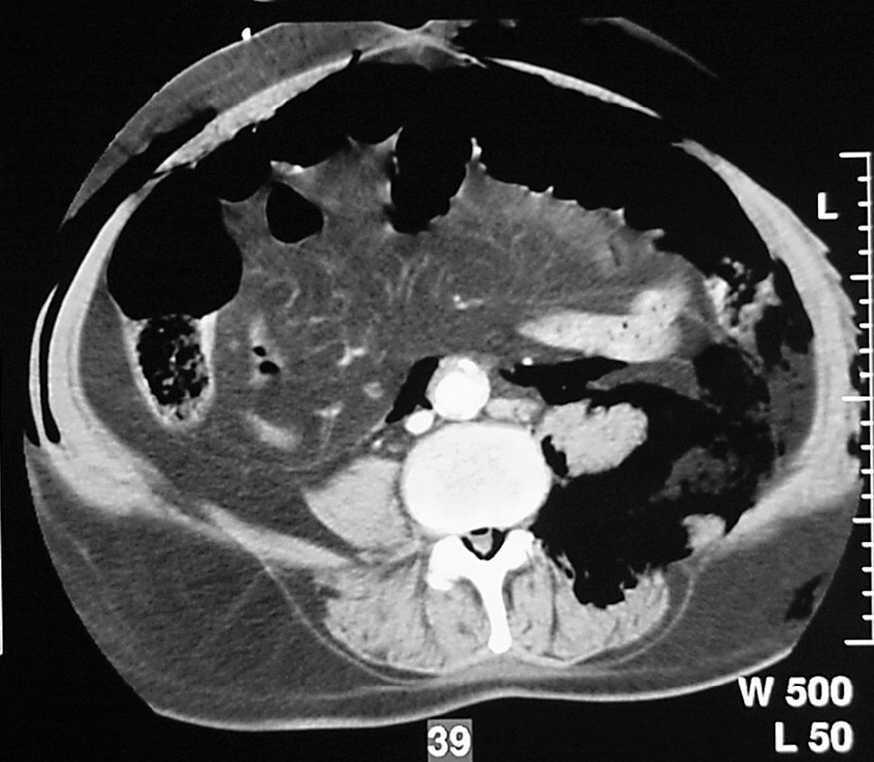

Paciente de 69 años, diabético de larga evolución con deficiente control de su glucemia y con arteriopatía periférica. A las 24 h de la amputación supracondílea del miembro inferior izquierdo debido a una isquemia crónica presentó un cuadro clínico de agitación psicomotriz importante, dolor intenso, fiebre, taquipnea, hipotensión y oligoanuria. En la exploración se observó edema, equimosis y crepitación desde la zona amputada hasta fosa ilíaca izquierda e incluso en el hipocondrio izquierdo, con un intenso olor fétido. En los datos de laboratorio destacaba: 44.100 leucocitos/ml (92% polimorfonucleares), hemoglobina 6,3 g/dl (descenso de 6 puntos en el hematócrito), creatincinasa 3.295 U y actividad de protrombina del 52%. Se realizó una tomografía computarizada urgente que mostró una tumefacción de partes blandas que afectaba a la totalidad del muslo izquierdo y al área genital, con la formación de bolsas de aire entre la fascia y los planos musculares (fig. 1) y presencia de aire en el espacio retroperitoneal izquierdo con desplazamiento anterior del riñón ipsolateral (fig. 2). Se practicaron varias incisiones de drenaje, con extirpación de tejidos necrosados y lavado de la zona con salida de exudado sanguinolento (se observaron gérmenes del género Clostridium en la visión directa). Ingresó en la unidad de cuidados intensivos y falleció 6 h después por shock séptico.

Fig. 2.